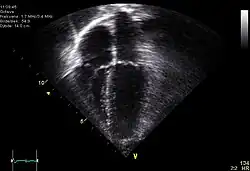

Diagnostic method | ECG, chest x-ray, bedside echocardiogram |

Diagnosis of traumatic cardiac arrest is initially made with electrocardiogram with EMS or in the emergency department. Clinicians will also order diagnostic testing that may include chest x-ray, bedside ultrasound and echocardiogram, and blood gas levels. A type and cross will be ordered to match the patient to receive blood transfusion if necessary.